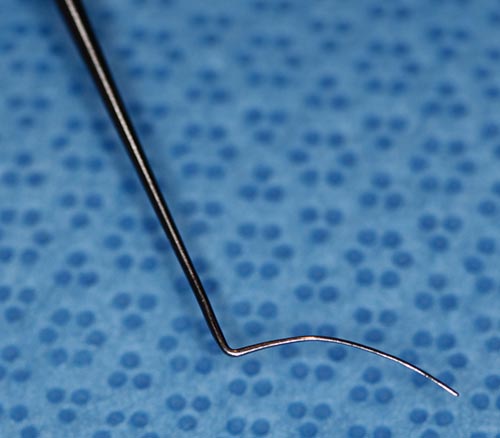

Hook, Sinskey

Sinsky

Catalog: Storz E545

Typical Use(s): Rotate IOL; Position haptics

Hook, Sinskey (Enlarged)

Sinsky

Catalog: Storz E545

Typical Use(s): Rotate IOL; Position haptics